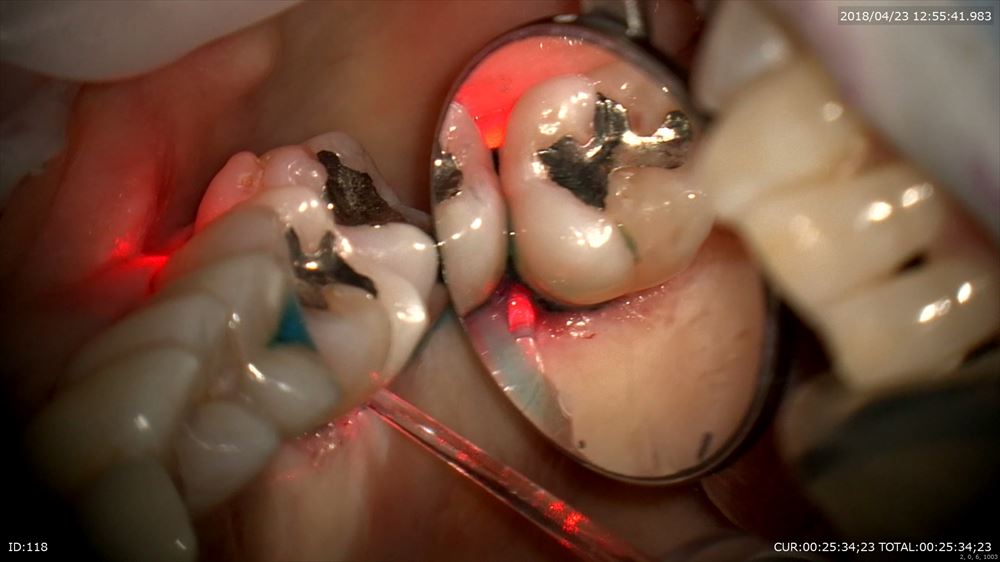

レーザー

こんなにデブライドメントしてもこの様に乳頭も傷をつけず

切り傷などありません。裸眼やルーペとは丁寧さの次元が違います。だから痛くない!!!